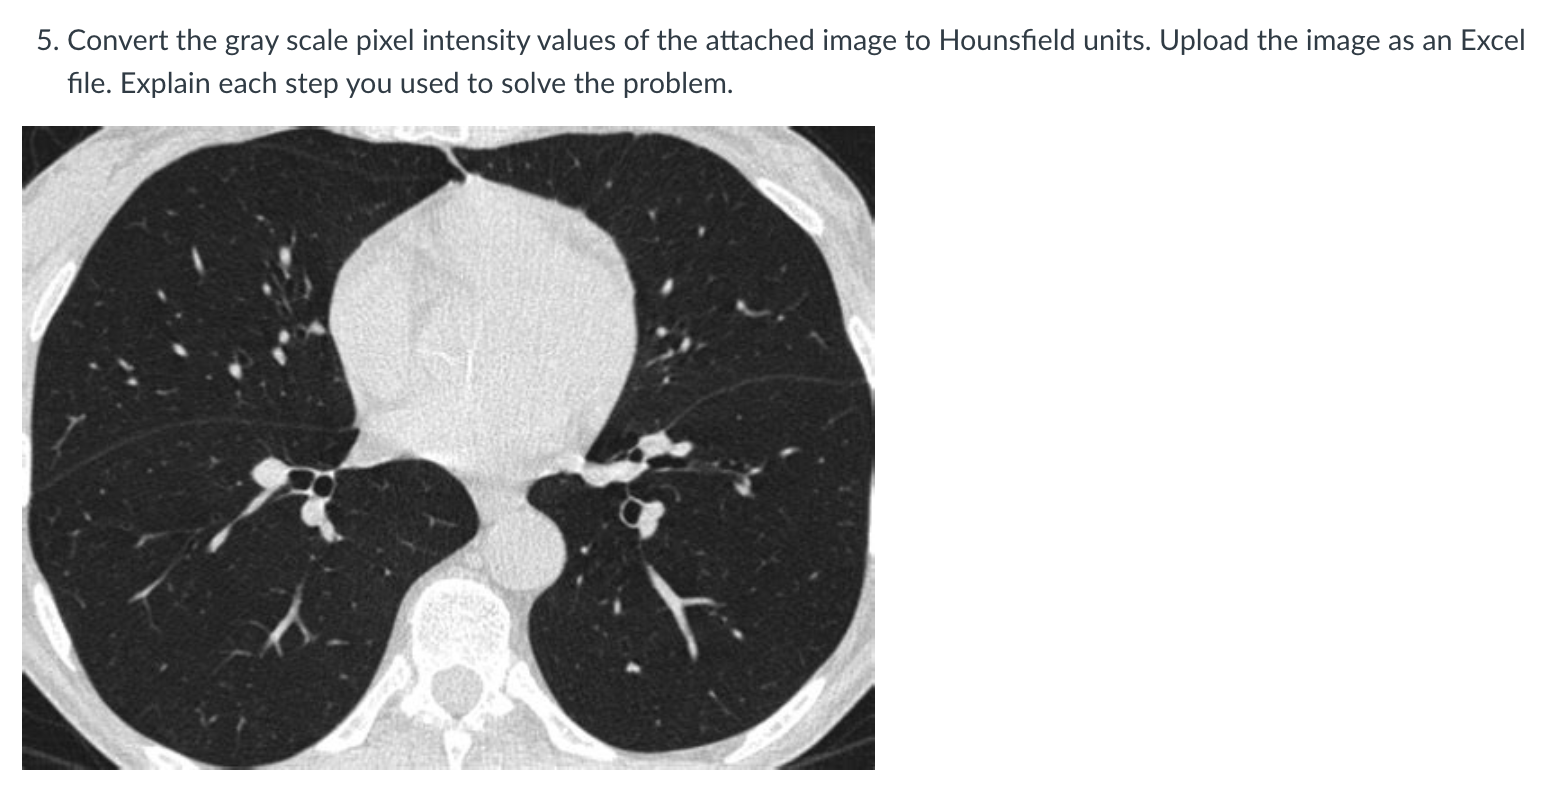

5. Convert the gray scale pixel intensity values of the attached image to Hounsfield units. Upload the image as an Excel file. Explain each step you used to solve the